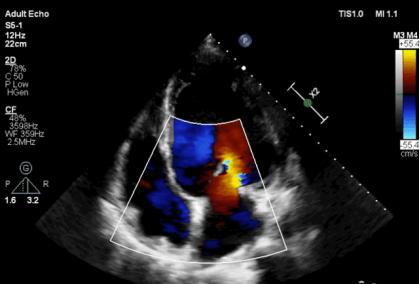

▲ 术前心超显示:患者重度二尖瓣反流

68岁的王大爷,7年前因主动脉瓣重度反流、二尖瓣重度反流做了主动脉瓣置换和二尖瓣成形术。然而,近年来王大爷二尖瓣反流复发并逐年加重,药物治疗效果很差。当他前往医院求诊时,心衰症状已十分严重。心超检查提示:患者左心室显著扩大为舒张末内径86mm,收缩末内径73mm,超过正常人一倍,而反映心肌收缩力的重要指标EF值则降低为30%,仅为正常人的一半。这意味着,患者的心脏明显扩大至正常人的两倍,心脏功能极差,随时可能诱发心脏衰竭导致死亡。